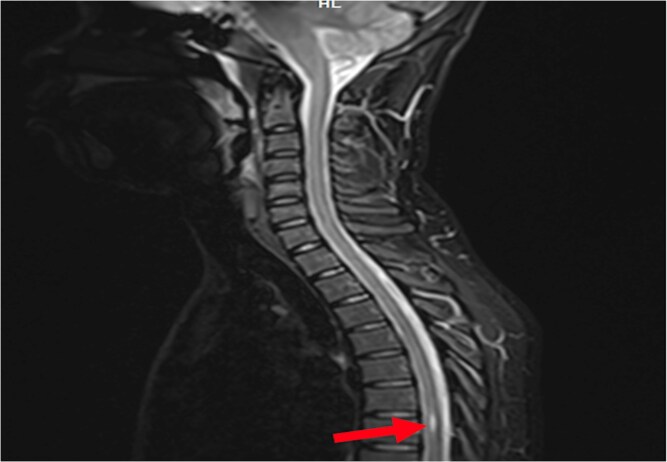

Introduction: Syringomyelia is a rare pathology which is rarely revealed by urinary urgency. We report the case of a 20-year-old man with persistent urinary urgency and pollakiuria for two years, with no identifiable organic cause despite a thorough urological work-up. A transient episode of lower limb atony prompted spinal MRI, which revealed an isolated syrinx at the T6-T7 level, without associated Chiari malformation or conus medullaris involvement. The final diagnosis was vesico-sphincter dyssynergia with overactive bladder syndrome secondary to idiopathic thoracic syringomyelia. Conservative management, including anticholinergic therapy and psychological support, led to significant clinical improvement.

Conclusion: As illustrated by our case, syringomyelia may present exclusively with urinary symptoms. However, such presentation is uncommon. This case highlights the importance of considering spinal cord pathology in the differential diagnosis of unexplained urinary symptoms, even in the absence of overt neurological deficits.